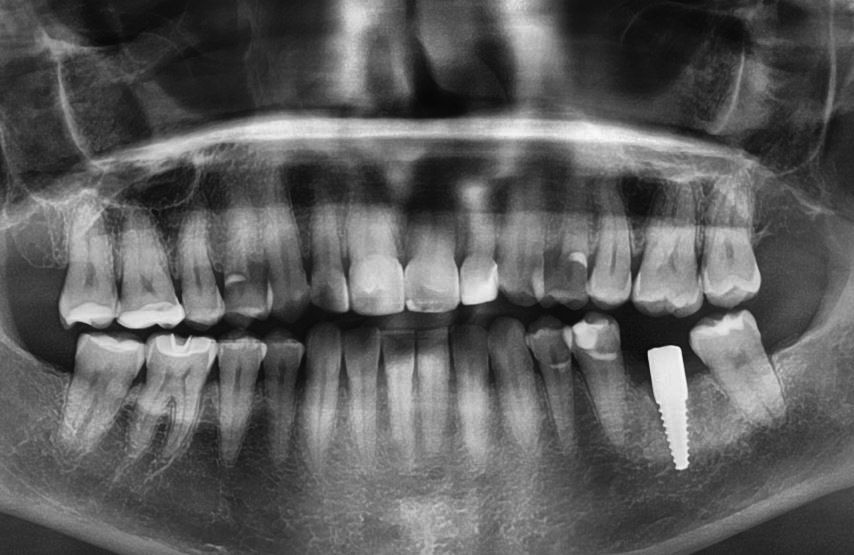

Dies im Gegensatz zu diesem Patienten:

Es liegen hier viele wurzelbehandelte Zähne vor, welche zudem schlecht gemacht wurden, und entsprechend viele Hinweise auf gesundheitlich belastende Zustände.

Schlechte Wurzelbehandlungen sind auch erkennbar an den unregelmässigen Rändern welche die meisten der wurzelbehandelten Zähnen aufweisen (vergleichen Sie mit dem grünen guten wurzelbehandelten Zahn.).

Sollte so jemanden sich über chronische Entzündungen beschweren, so ist es Pflicht von jedem Arzt und Zahnarzt, solche potentielle Herde in den Überlegungen mit einzubeziehen.